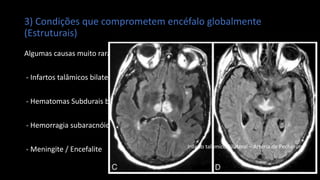

3) Condições que comprometem encéfalo globalmente

(Estruturais)

Algumas causas muito raras:

- Infartos talâmicos bilaterais

- Hematomas Subdurais bilaterais

- Hemorragia subaracnóidea

- Meningite / Encefalite Infarto talâmico Bilateral – Artéria de Pecheron